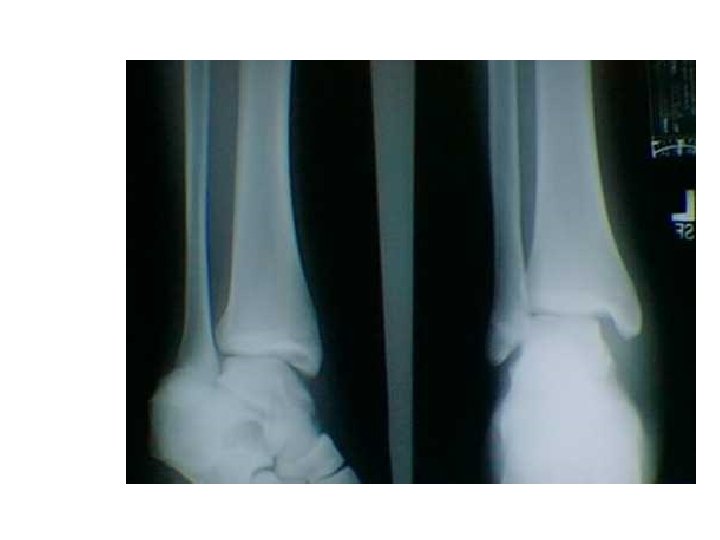

Distal Fibula fracture with associated medial deltoid ligament disruption. This injury is frequently the result of the foot being planted with a valgus load applied to the leg.

Notice the disruption of the medial deltoid ligament and the widening between the medial malleolus and the talus. This is indicative of a ruptured deltoid ligament.